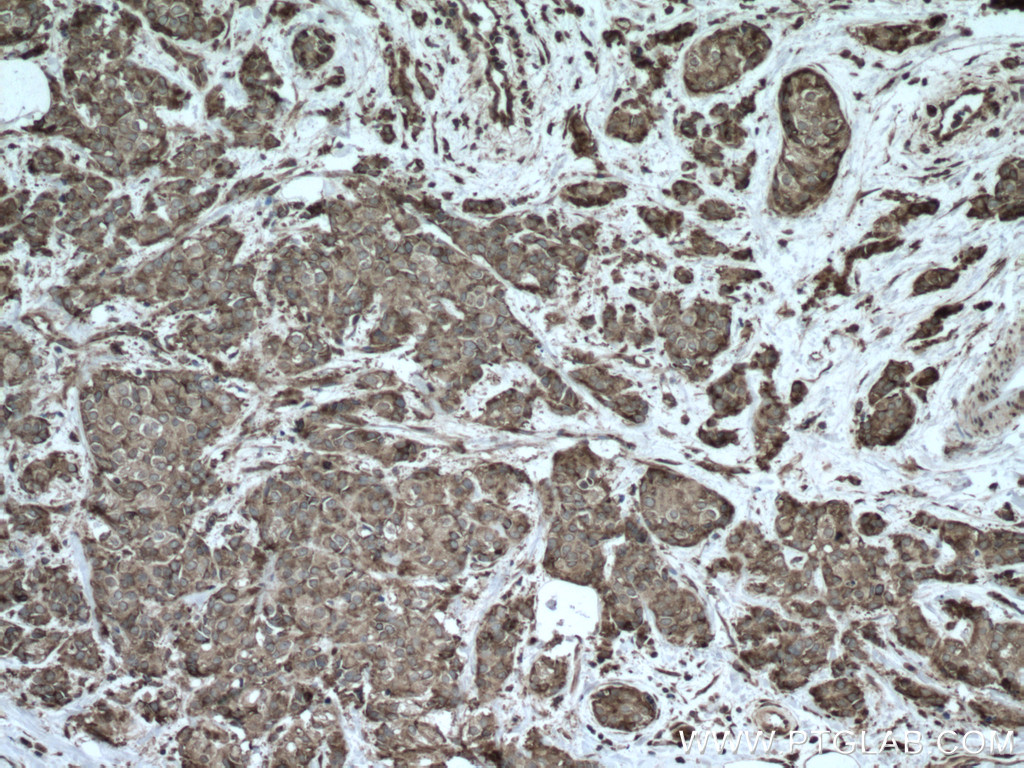

| Positive IHC detected in | human lung cancer tissue, human colon cancer tissue Note: suggested antigen retrieval with TE buffer pH 9.0; (*) Alternatively, antigen retrieval may be performed with citrate buffer pH 6.0 |

| Immunohistochemistry (IHC) | IHC : 1:50-1:500 |